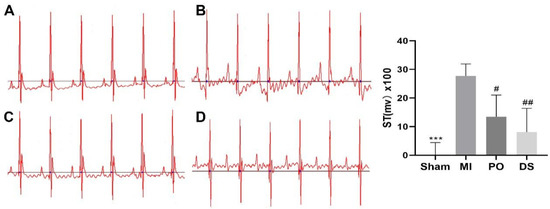

2.2. Effect of PO on Electrocardiogram (ECG) in MI Mice